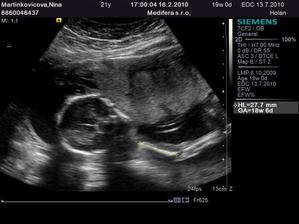

♥ V pondelok 16.11. som bola na sone - potvrdené tehotenstvo, bolo vidno len gestačný vačok

a žlté teliesko

♥ Všetko v poriadku, srdiečko bije, máme 1,6 cm a termín pôrodu sa posunul na 17.7. 🙂